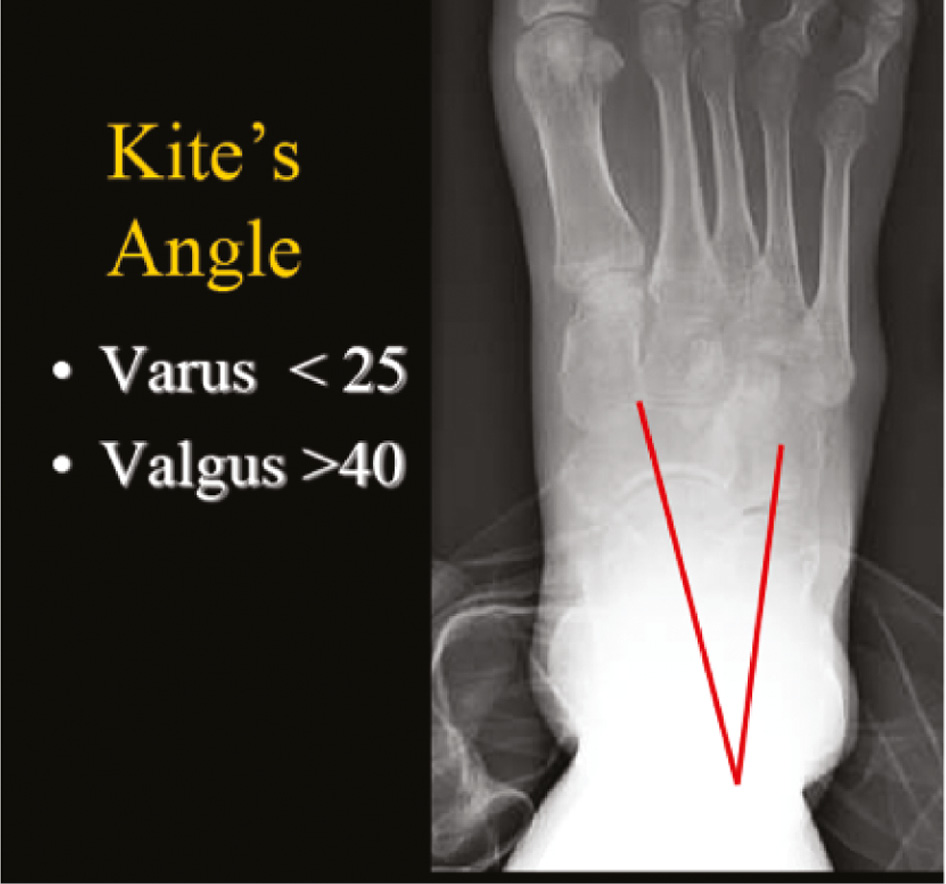

Radiographic evaluation of pes cavus is typically done with standing anteroposterior (AP) and lateral radiographs of the ankle as well as standing AP, lateral, and oblique radiographs of the foot. On the AP foot view, the talocalcaneal angle may be drawn to indicate the degree of hindfoot varus present. A talocalcaneal angle less than 20 to 25 degrees would be considered pathologic, with the normal range between 25 to 45 degrees (Figure 9). The talonavicular angle may additionally be drawn to assess the degree of forefoot adduction, with a value greater than 7 degrees indicating pathology. There may also be metatarsal overlap seen on this image that would indicate pronation of the forefoot. On the lateral foot view, Meary’s angle (lateral talo-first metatarsal angle) may be drawn. A break in this line is caused by plantarflexion of the first ray and a value more than 4 degrees apex dorsal indicates cavus (Figure 10). In the calcaneocavus foot with hindfoot dorsiflexion, the calcaneal pitch (or calcaneal inclination) is typically over 30 degrees (Figure 11).

Figure 9. An AP talocalcaneal angle less than 25 degrees is a sign of hind foot varus.

jposna20220035_fig9.jpg